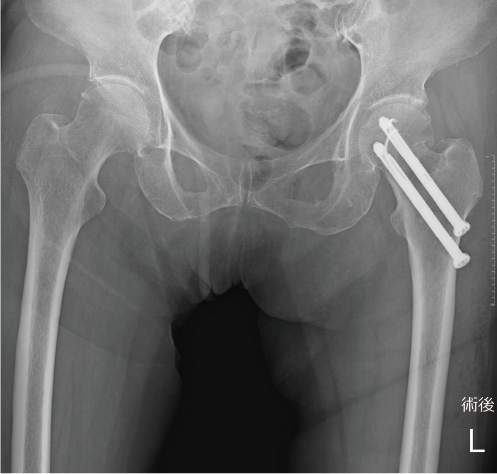

大腿骨頚部骨折は股関節内に骨折線があるため治りにくい骨折です。ほとんどずれていない(非転位型)大腿骨頚部骨折に対してはスクリューなどを用いた骨接合術を施行します(図1)。手術侵襲が少なく、術後感染や輸血の可能性も低く、歩行能力を回復しやすい骨折だと思います。

術後合併症として、骨がつかない可能性(15%以下)、大腿骨頭壊死症の可能性(20%以下)があり、これらが起こると再手術が必要になります。